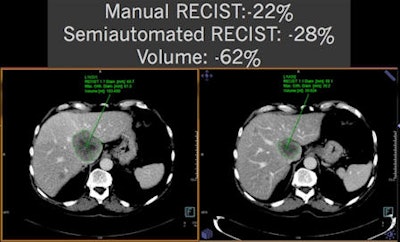

In a recent multicenter evaluation of manual versus semiautomated measurements of tumor volume in lymphoma patients, researchers studied 59 patients with malignant lymphoma. The patients had 290 lymph nodes (5 ± 2 per patient) measured at baseline and follow-up (after two cycles of chemotherapy).

Manual measurements were performed at five German university hospitals for long axis diameter, short axis diameter, and WHO area. Semiautomated measurements of the same parameters and volume were also performed.

Manual measurements took an average of 16.6 ± 13.3 seconds to produce. In the 41.9% of semiautomated measurements that were performed without needing corrections, volumetry took an average of 13.7 ± 7 seconds. However, volumetry required an average of 48.4 ± 30.2 seconds for the 58.1% of cases that needed manual correction. Taking into account all cases, volumetry was performed in an average time of 33.8 ± 29.0 seconds, twice as long as manual measurements.

In the multicenter study, manual WHO area calculations had a relative standard deviation of 19.2% and a standard deviation of 18.5%, while the semiautomated calculations had a relative standard deviation of 9.8% and standard deviation of 11%, Graser said.

The automated method also reduced misclassification of therapy response across all centers.